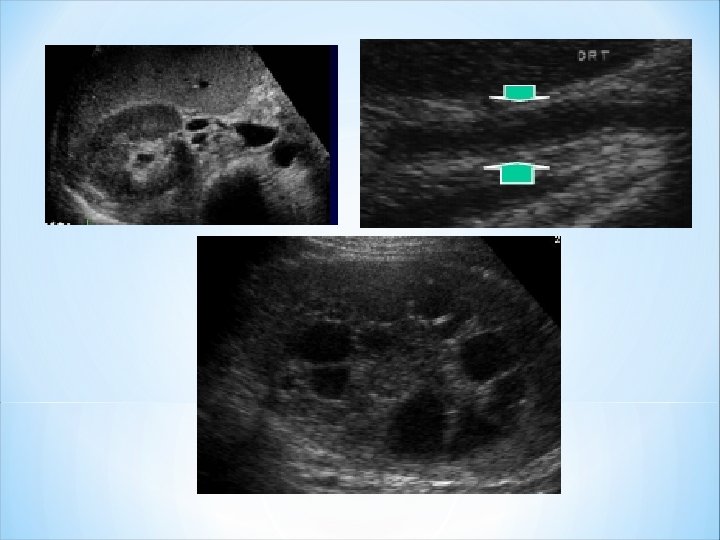

c- Pyélonéphrite xanthogranulomateuse: *Subaigu ou chronique. *Destruction progressive du parenchyme rénal à bas bruit. *Le diagnostic est anatomopathologique. *L'aspect en imagerie est variable et peu spécifique *Calculs = coralliformes de type struvite *Syndrome obstructif *Perte de la fonction rénale.

Pyélonéphrite xanthogranulomateuse du rein droit avec calcul pyélique Destruction du parenchyme rénal+ microabcès.